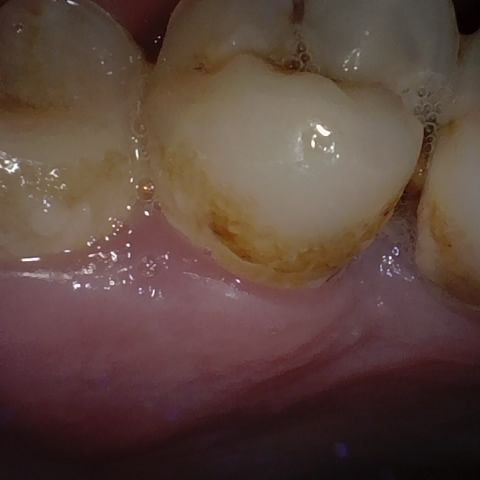

Annotated as "Good"